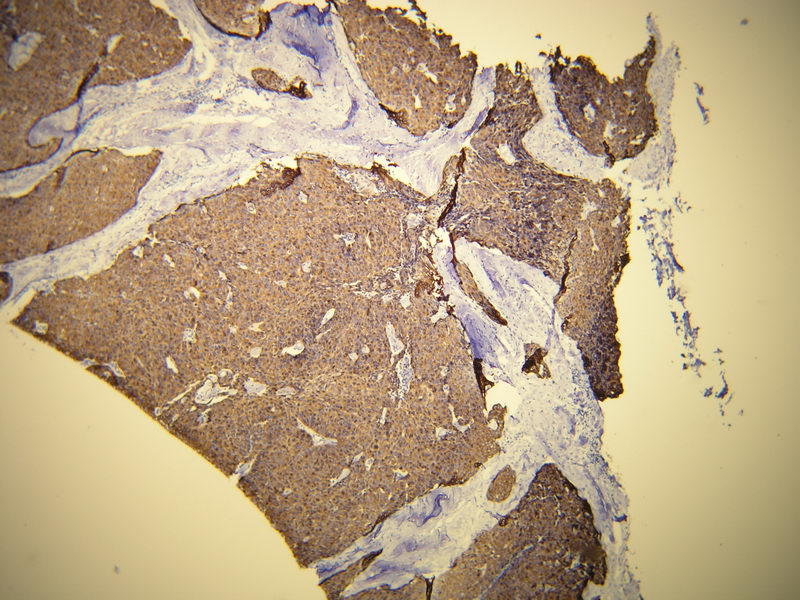

Anti-Cytokeratin 19

Rabbit clonal antibody

Product ID:DB 103 Category:IHC-P

Peptide derived from C-terminal region of human cytokeratin 19

IHC-P, dilution 1:100

Gallery

db103a db103b